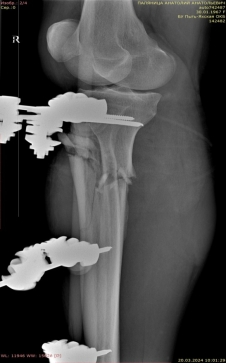

1) Мужчина, 35 лет. ДТП, водитель. Поступил в экстренном порядке. Диагноз — закрытый оскольчатый перелом дистального метаэпифиза правой большеберцовой кости, перелом наружной лодыжки правой голени со смещением отломков (рис. 1).

Рис. 1.